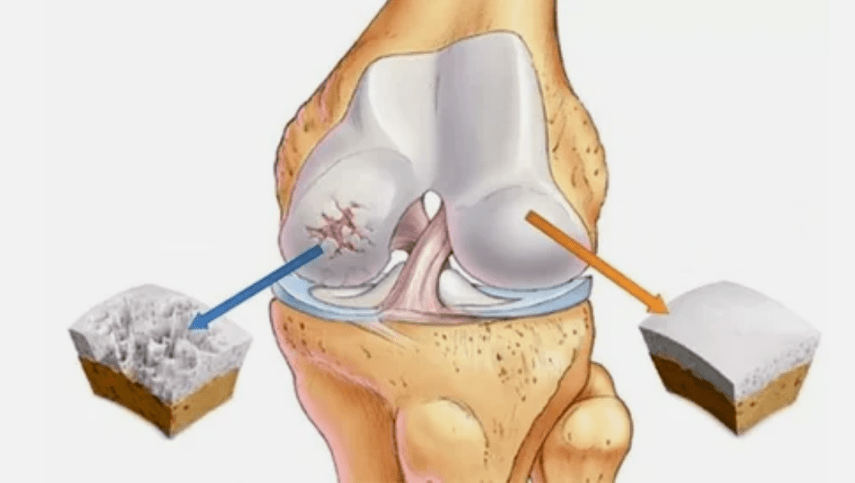

- Patologie di rivestimento ialina. Il diradamento della cartilagine porta alla sostituzione dei suoi tessuti patologici - strutture ossee.

- Le escrescenze anomali appaiono su cartilagine - osteofiti.

- Ridurre il divario nel divario dell'articolazione, che diventa evidente nella foto. Lo stadio della violazione è determinato dal diagnostico-Tantgenologo. Il paziente sente la complessità o l'incapacità di raddrizzare e piegare completamente l'arto;

- Deformazione articolare, la cartilagine acquisisce una forma irregolare, provocando curvatura;

- Fase 2. A causa della carenza di approvvigionamento, le cartucce necessarie vengono distrutte, le escrescenze ossee si formano sulla superficie della cartilagine. I dolori acquisiscono un carattere più pronunciato, intensificati dopo un lungo riposo, vengono eliminati da un piccolo travaglio fisico. Il dolore è accompagnato da infiammazione. I muscoli sono allungati, il che porta a funzioni motorie con disabilità deboli o medie.